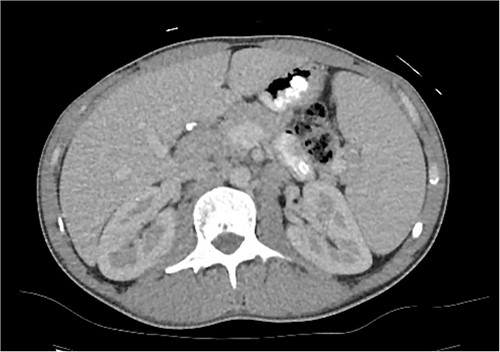

A computed tomography (CT) of the chest, abdomen and pelvis was organised and showed splenomegaly of 16.5 cm and suspicion of an enlarged lymph node between the head of the pancreas and the liver (Fig. 1). Magnetic resonance cholangiopancreatography (MRCP) did not further aid diagnosis.

CT axial slice of abdomen and pelvis demonstrating an enlarged lymph node at the porta hepatis and splenomegaly.

Despite investigations, the diagnosis was still unclear. Because of this, he underwent a laparoscopic excisional biopsy of the porta hepatis mass, situated postero-lateral to the common bile duct and common hepatic duct. This mass was visible on the abdominal CT scan (Fig. 1), yet much less clearly seen on the MRCP, which had been performed more recently. Biopsy results showed marked infiltration of PC with no evidence of Hodgkin like cells or evidence of metastatic malignancy. Human gammaherpesvirus 8 was negative with diffusely positive IgG PC. He was diagnosed with multicentric CD (MCD) and commenced siltuximab with ongoing reviews by the haematologists.